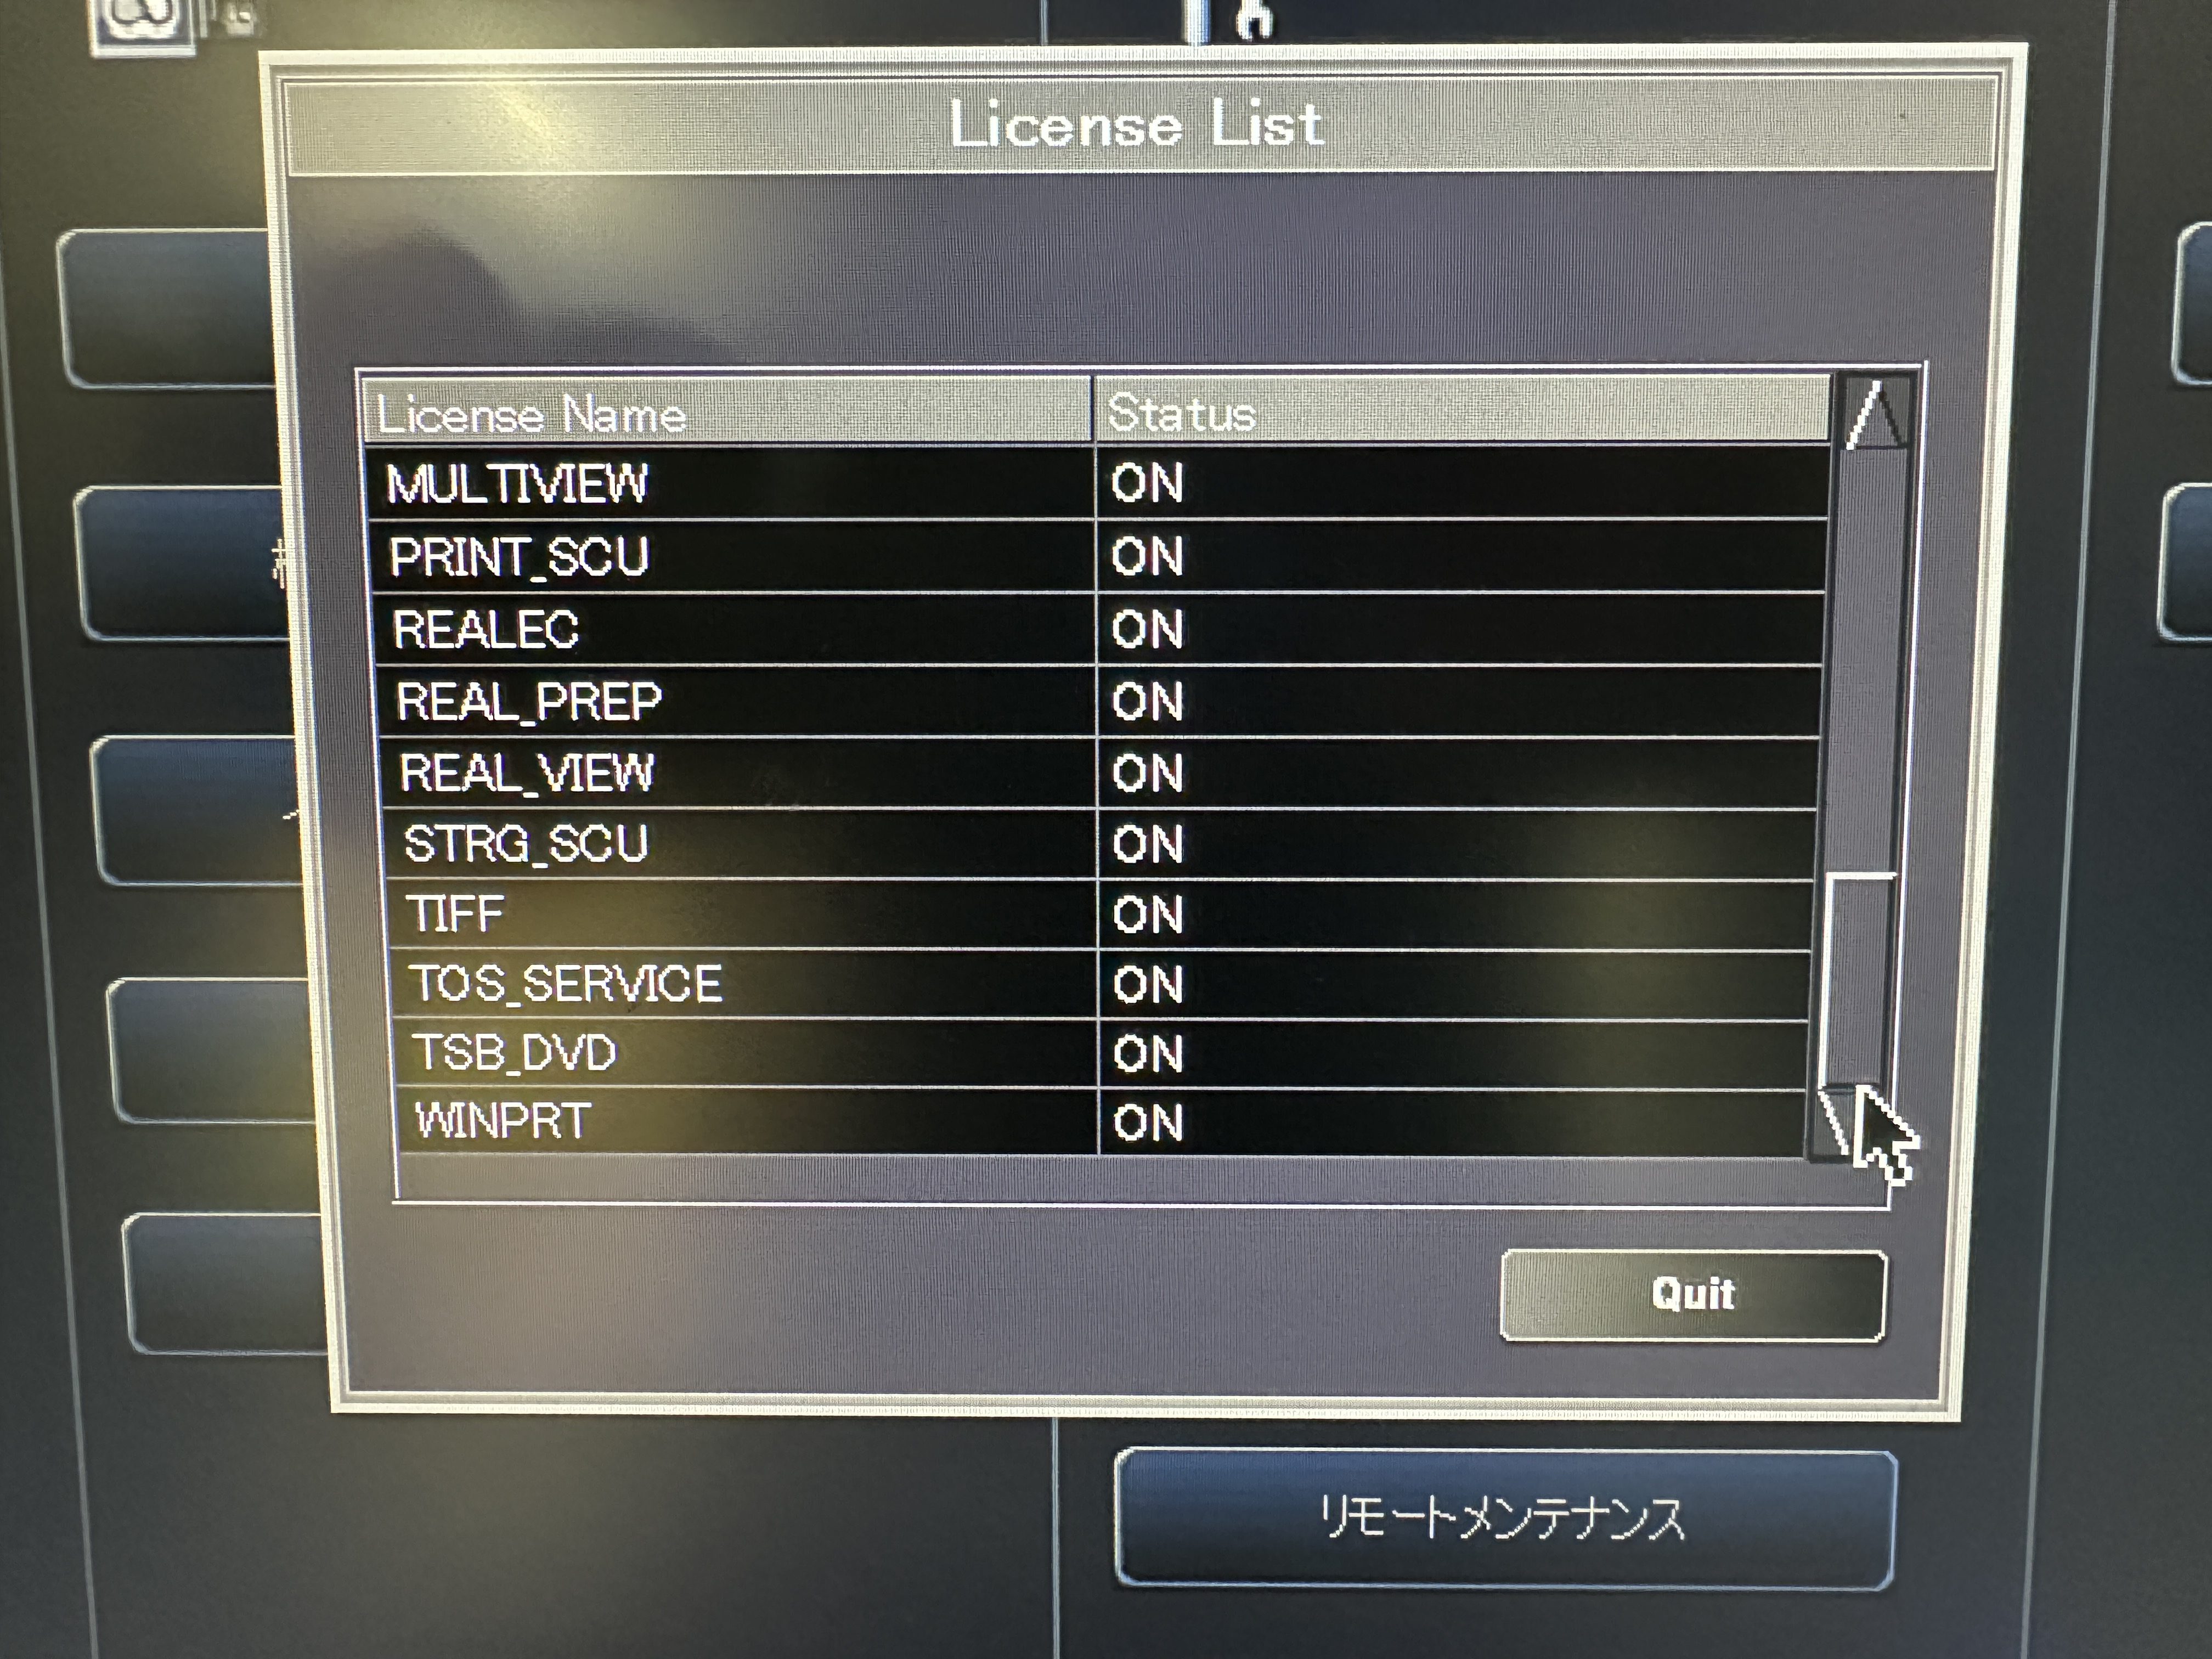

| Installed Options | : | ALATO_3DVIEWER, ALATO_MULTISLICECT, ALATO_STANDARD, DCM_CDR, DIM_EXP, DOUBLESLICE, D_PRT_BW, D_PRT_COLOR, MULTIVIEW, PRINT_SCU, REALEC, REAL_PREP, REAL_VIEW, STRG_SCU, TIFF, TOS_SERVICE, TSB_DVD, WINPRT |